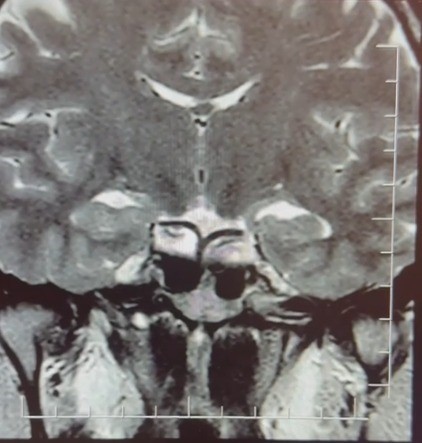

Yapılan ileri tetkiklerde hastaya hipofiz MR çekildiğini aktaran Çiftçoğlu, "MR sonucunda beynin hipofiz bölgesinde ‘prolaktinoma’ olarak adlandırılan bir tümör tespit ettik. Bu tümör, prolaktin hormonunun aşırı salgılanmasına neden oluyor. Genellikle iyi huylu olup ilaç tedavisiyle kontrol altına alınabiliyor" diye konuştu.

Gebelik belirtilerine benzer şikayetlerin farklı hastalıkların habercisi olabileceğine dikkat çeken Çiftçoğlu, "Prolaktin hormonu aslında beyinde hipofiz bezinden salgılanan ve süt salınımını sağlayan hormondur. Bunun yüksek olduğunu tespit ettikten sonra hastada hipofiz MR çektirdik. Çektiğimiz beyin MR’ında hastanın hipofiz dediğimiz bölgede kitleyi tümörü tespit ettik. Prolaktinoma dediğimiz bir tümör. Prolaktinoma tümörü beyinde hipofiz bölgesinde bulunmakta olup prolaktin hormonunun aşırı miktarda salgılanmasını sağlayan bir tümördür. Bu durumda iyi huyludur, kanserleşme olmasını çok yoktur. Dolayısıyla ilaçla tedavisi mümkündür ama gebelik şikayetlerini de andırdığı için mutlaka ayırıcı tanıda akılda tutulması gereken bir durumdur. Hasta da bizle öğrendi ’hamileyim’ diye geldi hasta, gebelik muayenesi olma talebiyle geldi ancak biz tümörü tespit ettik. Önce gebe olmadığını tespit ettik ve sonra ’Bu şikayetlere sebep olabilecek ne var?’ diye araştırdığımızda bu durum ortaya çıktı. Yani tümörü de aynı gün içerisinde değil birkaç gün sonra ileri tetkik sayesinde öğrenmiş oldu" dedi.